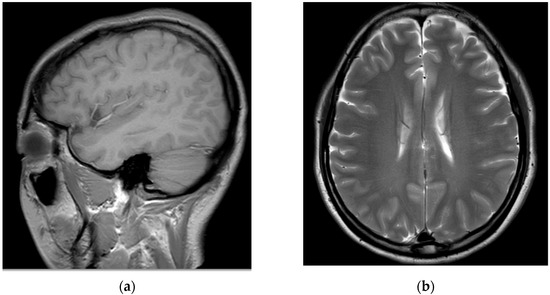

Before visiting our hospital, a 35-year-old woman with no specific medical history visited a spine hospital complaining of posterior neck pain radiating to the left upper arm. These symptoms appeared 6 months before she was admitted at the spinal hospital and had worsened to a Visual Analog Scale (VAS) score of 6 at the time of admission. No motor weakness or sensory changes were observed upon physical examination at the time of admission. However, numbness was observed in the left arm during the Spurling test. Magnetic resonance imaging (MRI) of the cervical spine showed a herniated intervertebral disc at the C5/6 level and left C6 nerve impingement due to left foraminal extrusion (Figure 1).

Figure 1.

Cervical spine magnetic resonance images obtained before the procedure. A herniated intervertebral disc at the C5/6 level and left C6 nerve impingement due to a left foraminal extrusion are observable on the (a) T2-weighted sagittal image and (b) T2-weighted axial image of the C5/6 level.